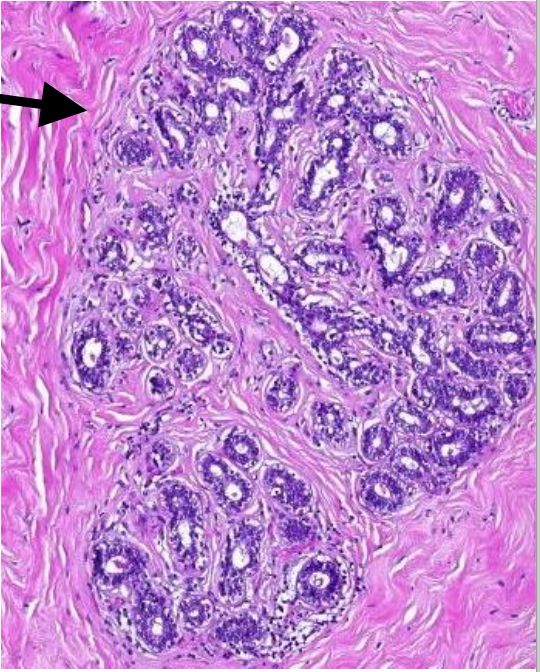

Welk preparaat

invasief ductaal carcinoom (borst)

pathologie ductaal carcinoom

zware verstoring architectuur van de klierbuizen

basaal membraan doorbroken

solitaire tumorale cellen en nestjes

anisocytose, anisonucleose en mitose

welke kleuringen om te bewijzen dat het gaat om een invasief carcinoom

calponine of p63